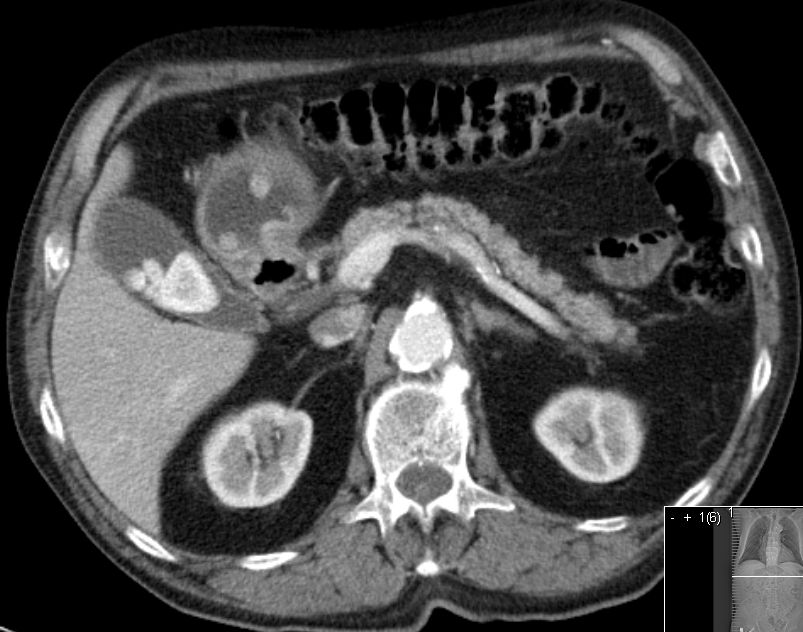

| Pylorus | 81-jähriger Mann mit stenosierendem Magenkarzinom des Pylorus, z.T. polypöse Strukturen.

Gering differenziertes Adenokarzinom, G3, diffuser Typ. N.B. Gallensteine![]() | |||